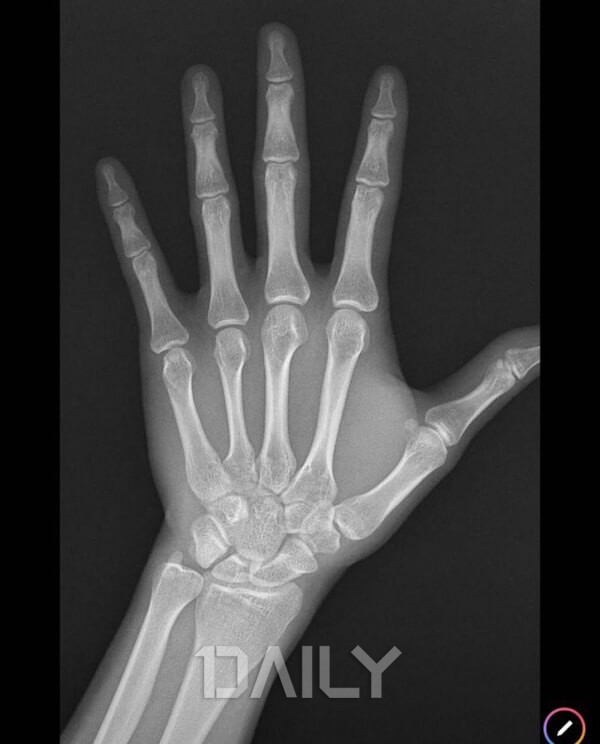

¼ºÀåÆÇ ¼¼Æ÷´Â Á¡Â÷ ½Ã°£ÀÌ Áö³ª¸é¼ µüµüÇÑ »À·Î ¹Ù²î¸é¼ Ȱµ¿ÀÌ ÁÙ¾îµé°Ô µÇ´Âµ¥, ¿©ÀÚÀÇ °æ¿ì ¾à 15¼¼, ³²ÀÚÀÇ °æ¿ì 17¼¼°¡ µÇ¸é ¼ºÀåÀÌ ¸ØÃá´Ù°í ¾Ë·ÁÁ® ÀÖ½À´Ï´Ù. ¼ºÀåÆÇÀÌ ´ÝÈ÷°í ³ª¼µµ 20¼¼ ÀüÈıîÁö ۰¡ ÀÚ¶ó±â´Â ÇÏÁö¸¸ ¼ºÀåÆÇÀÌ ´ÝÈ÷±â Àü°ú ºñ±³ÇßÀ» ¶§ Àý¹Ý Á¤µµ·Î ¼ºÀå ¼öÄ¡°¡ ÁÙ¾îµé°Ô µË´Ï´Ù. ÀÌ ½Ã±â¸¦ Áö³ª ¼ºÀåÆÇÀÌ ¿ÏÀüÈ÷ ´ÝÈù ÈÄ¿¡´Â »À ¼ºÀåÀÌ ´õ ÀÌ»ó ÀÌ·ç¾îÁöÁö ¾Ê½À´Ï´Ù.